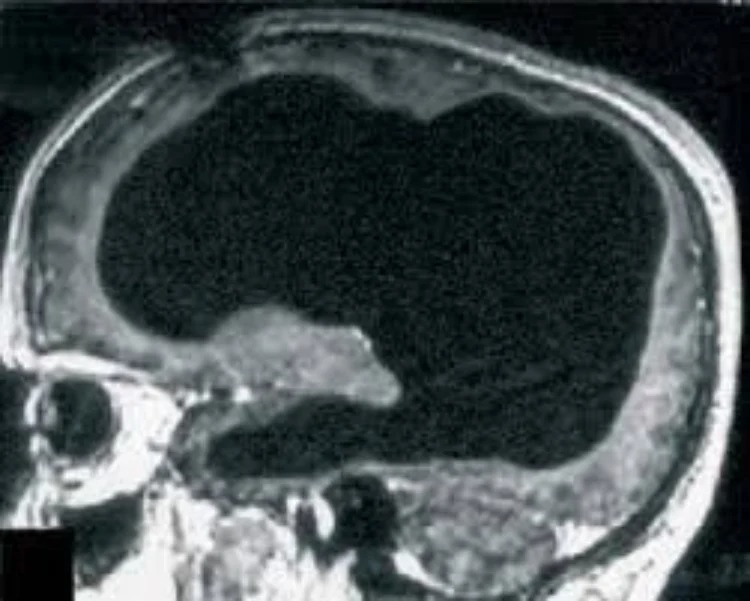

Những tưởng bệnh đã được khắc phục, nhưng 30 năm sau, khi ông bước sang tuổi 44, tình trạng yếu chân trái tái phát. Các bác sĩ tại Bệnh viện Marseille (Pháp) chỉ định chụp CT và MRI, và kết quả đã khiến toàn bộ ekip y khoa sửng sốt: não của ông gần như biến mất. Khoảng 75% đến 90% mô não bị tiêu hủy, thay vào đó là các khoang rỗng chứa đầy dịch não tủy.

Những hình ảnh chụp cộng hưởng từ cho thấy các thùy trán, thùy đỉnh, thùy thái dương và thùy chẩm – những khu vực đảm nhiệm tư duy, ngôn ngữ, cảm xúc và thị giác đều teo lại thành một lớp mỏng bao quanh hộp sọ. Trong điều kiện bình thường, tổn thương ở những vùng này sẽ dẫn đến suy giảm nghiêm trọng nhận thức, trí nhớ hoặc thậm chí rơi vào trạng thái sống thực vật.